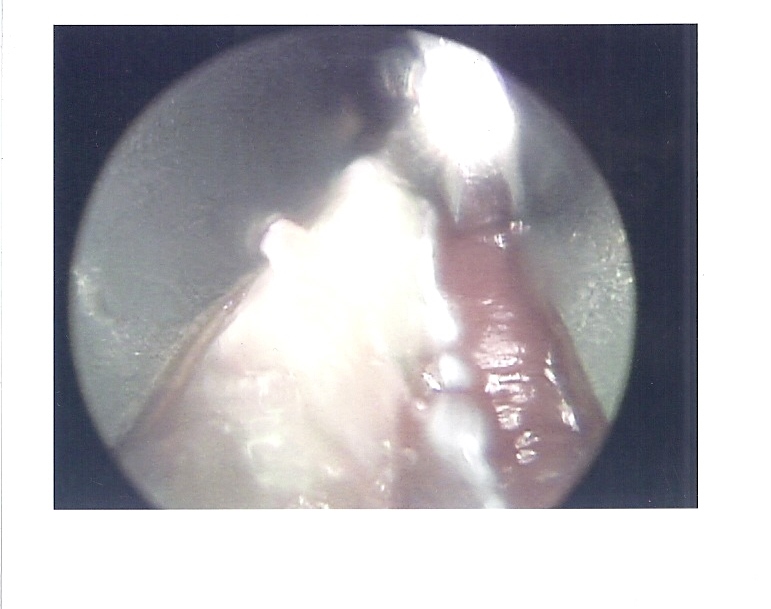

Here are the Endoscopic Camera Surgical Photos, (click on photos to enlarge)

Here is my YouTube video of Dr. Gent visiting me after I was well awake in the recovery room. The surgery was about 40 minutes and Dr. Gent said there was a good release of the muscle and complete full-range ankle dorsiflexion after the slice through the Gastroc and Soleus Aponeurosis. Surgery started before 9am and I was back to my hotel around noontime. The surgery was done under General Anesthesia. My lower leg is very comfortable in its plaster splinting and ace wraps and my TENS unit leads are applied underneath for help in pain control.